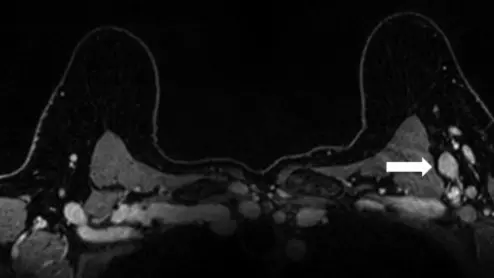

axillary lymphadenopathy after COVID booster

Experts recently gained a better understanding of how axillary lymphadenopathy presents on breast MRI following COVID boosters.